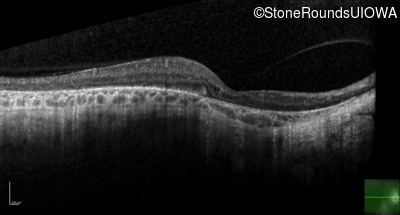

| Age at visit: 47 years |

| XL Choroideremia | CHM | Insertion of 212.3kb of Chr. 3 in intron 2 (IVS2+15,016 ins 212.3kb) | XL |